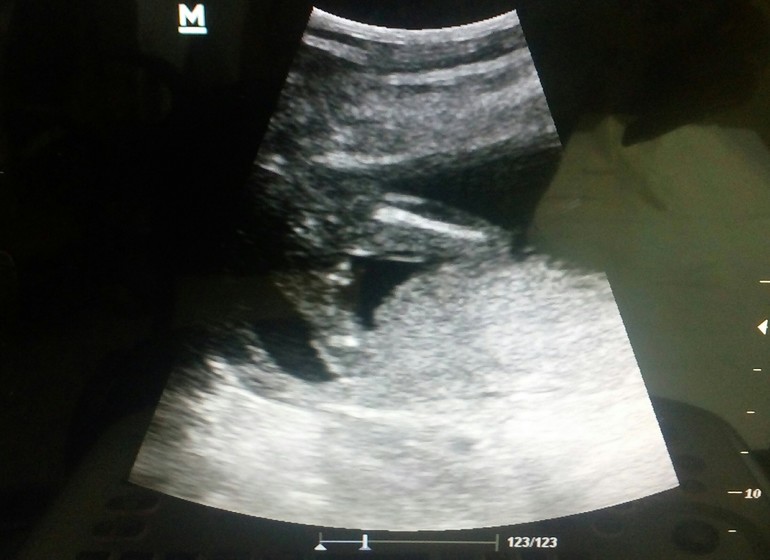

В 16,3 недели отправилась на УЗИ, так как планируется отдых и ради собственного спокойствия лучше перестраховаться. Все хорошо, шейка в норме, ляля барахтается и нам объявили пол. И это мальчик! Муж счастлив, я в растерянности, предчувствие было на девочку, а тут защитник и без вариантов сомнений, чётко продемонстрировал органы свои🙈🙊🙉